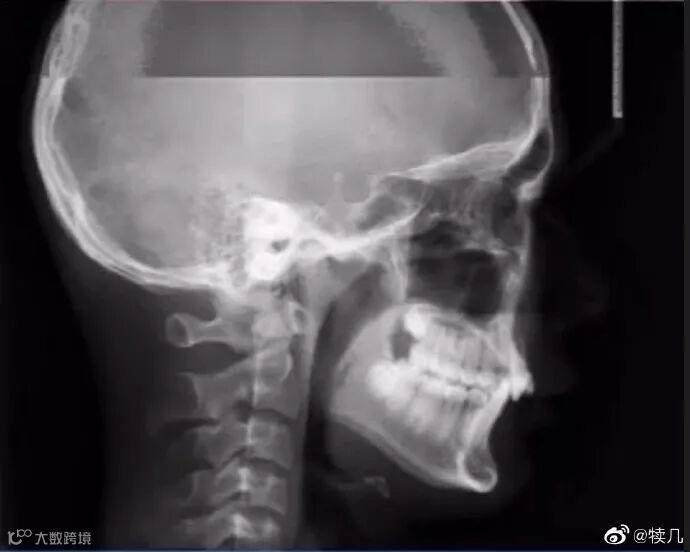

拍牙片时打了一个哈欠

一定要忍住不笑

糟了,困了!

就打一次哈欠

医生:这拍牙片的是毒液吧